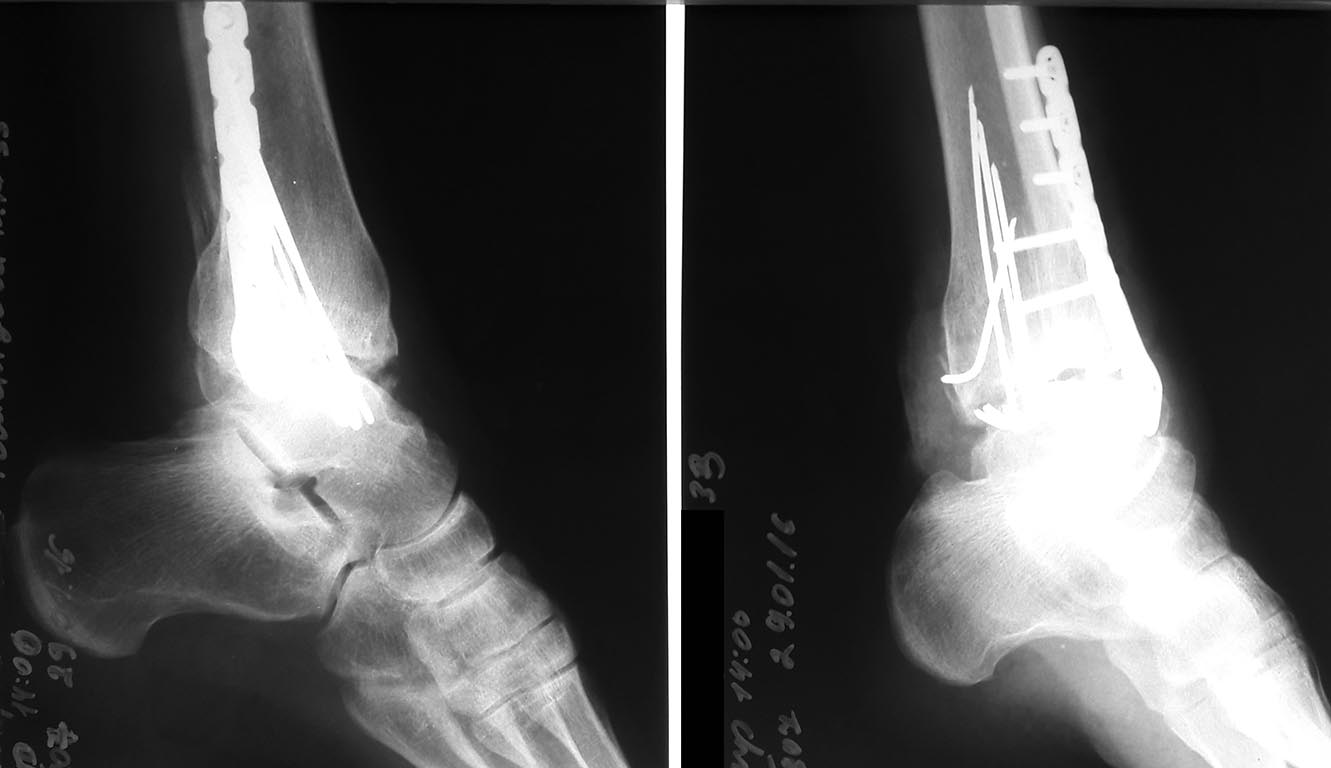

фото 1-2016